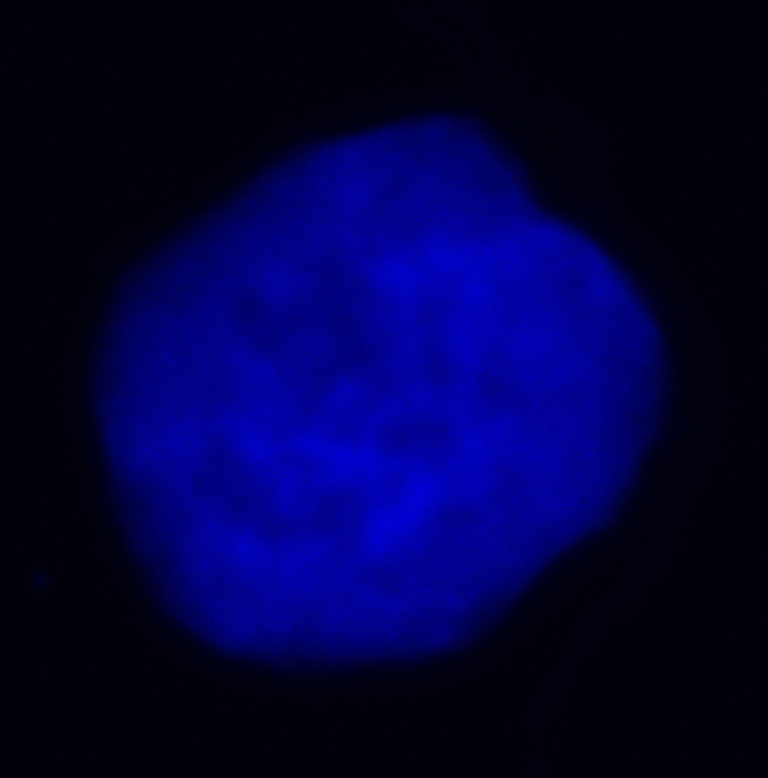

This image depicts a leukemia cell that is stained using immunofluorescence. The blue staining is DAPI, which intercalates DNA. The green color represents labeled replication forks. My thesis project attempts to elucidate how perturbed replication forks induce epigenetic reprogramming in leukemia. In leukemia, replication stress can lead to broad epigenetic changes and alterations in cell state. I hope to contribute to a better understanding of how this phenomenon occurs, which could eventually lead to the discovery of new therapeutic targets for blood cancers.